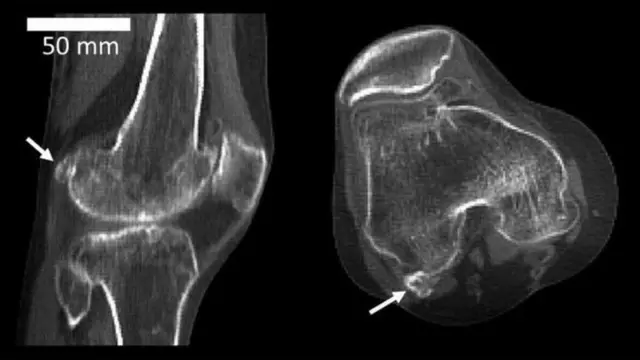

این استخوان که فابلا نام دارد که به معنای لوبیای کوچک است. این استخوان از دسته استخوانهای سزاموئید است، یعنی استخوانهایی که در دخالت تاندون یک ماهیچه رشد میکنند مثل استخوان کشکک.

منبع تصویر، IMPERIAL COLLEGE LONDON

این بررسی نشان داد از سال ١٩١٨ تا ٢٠١٨، یعنی در صد سال گذشته فراوانی این استخوان بیش از سه برابر شده است. پژوهشگران به این نتیجه رسیدند که در سال ١٩١٨ حدود یازده درصد جمعیت دنیا در زانویشان استخوان فابلا داشتند اما در سال ٢٠١٨ این میزان به ٣٩ درصد رسید.